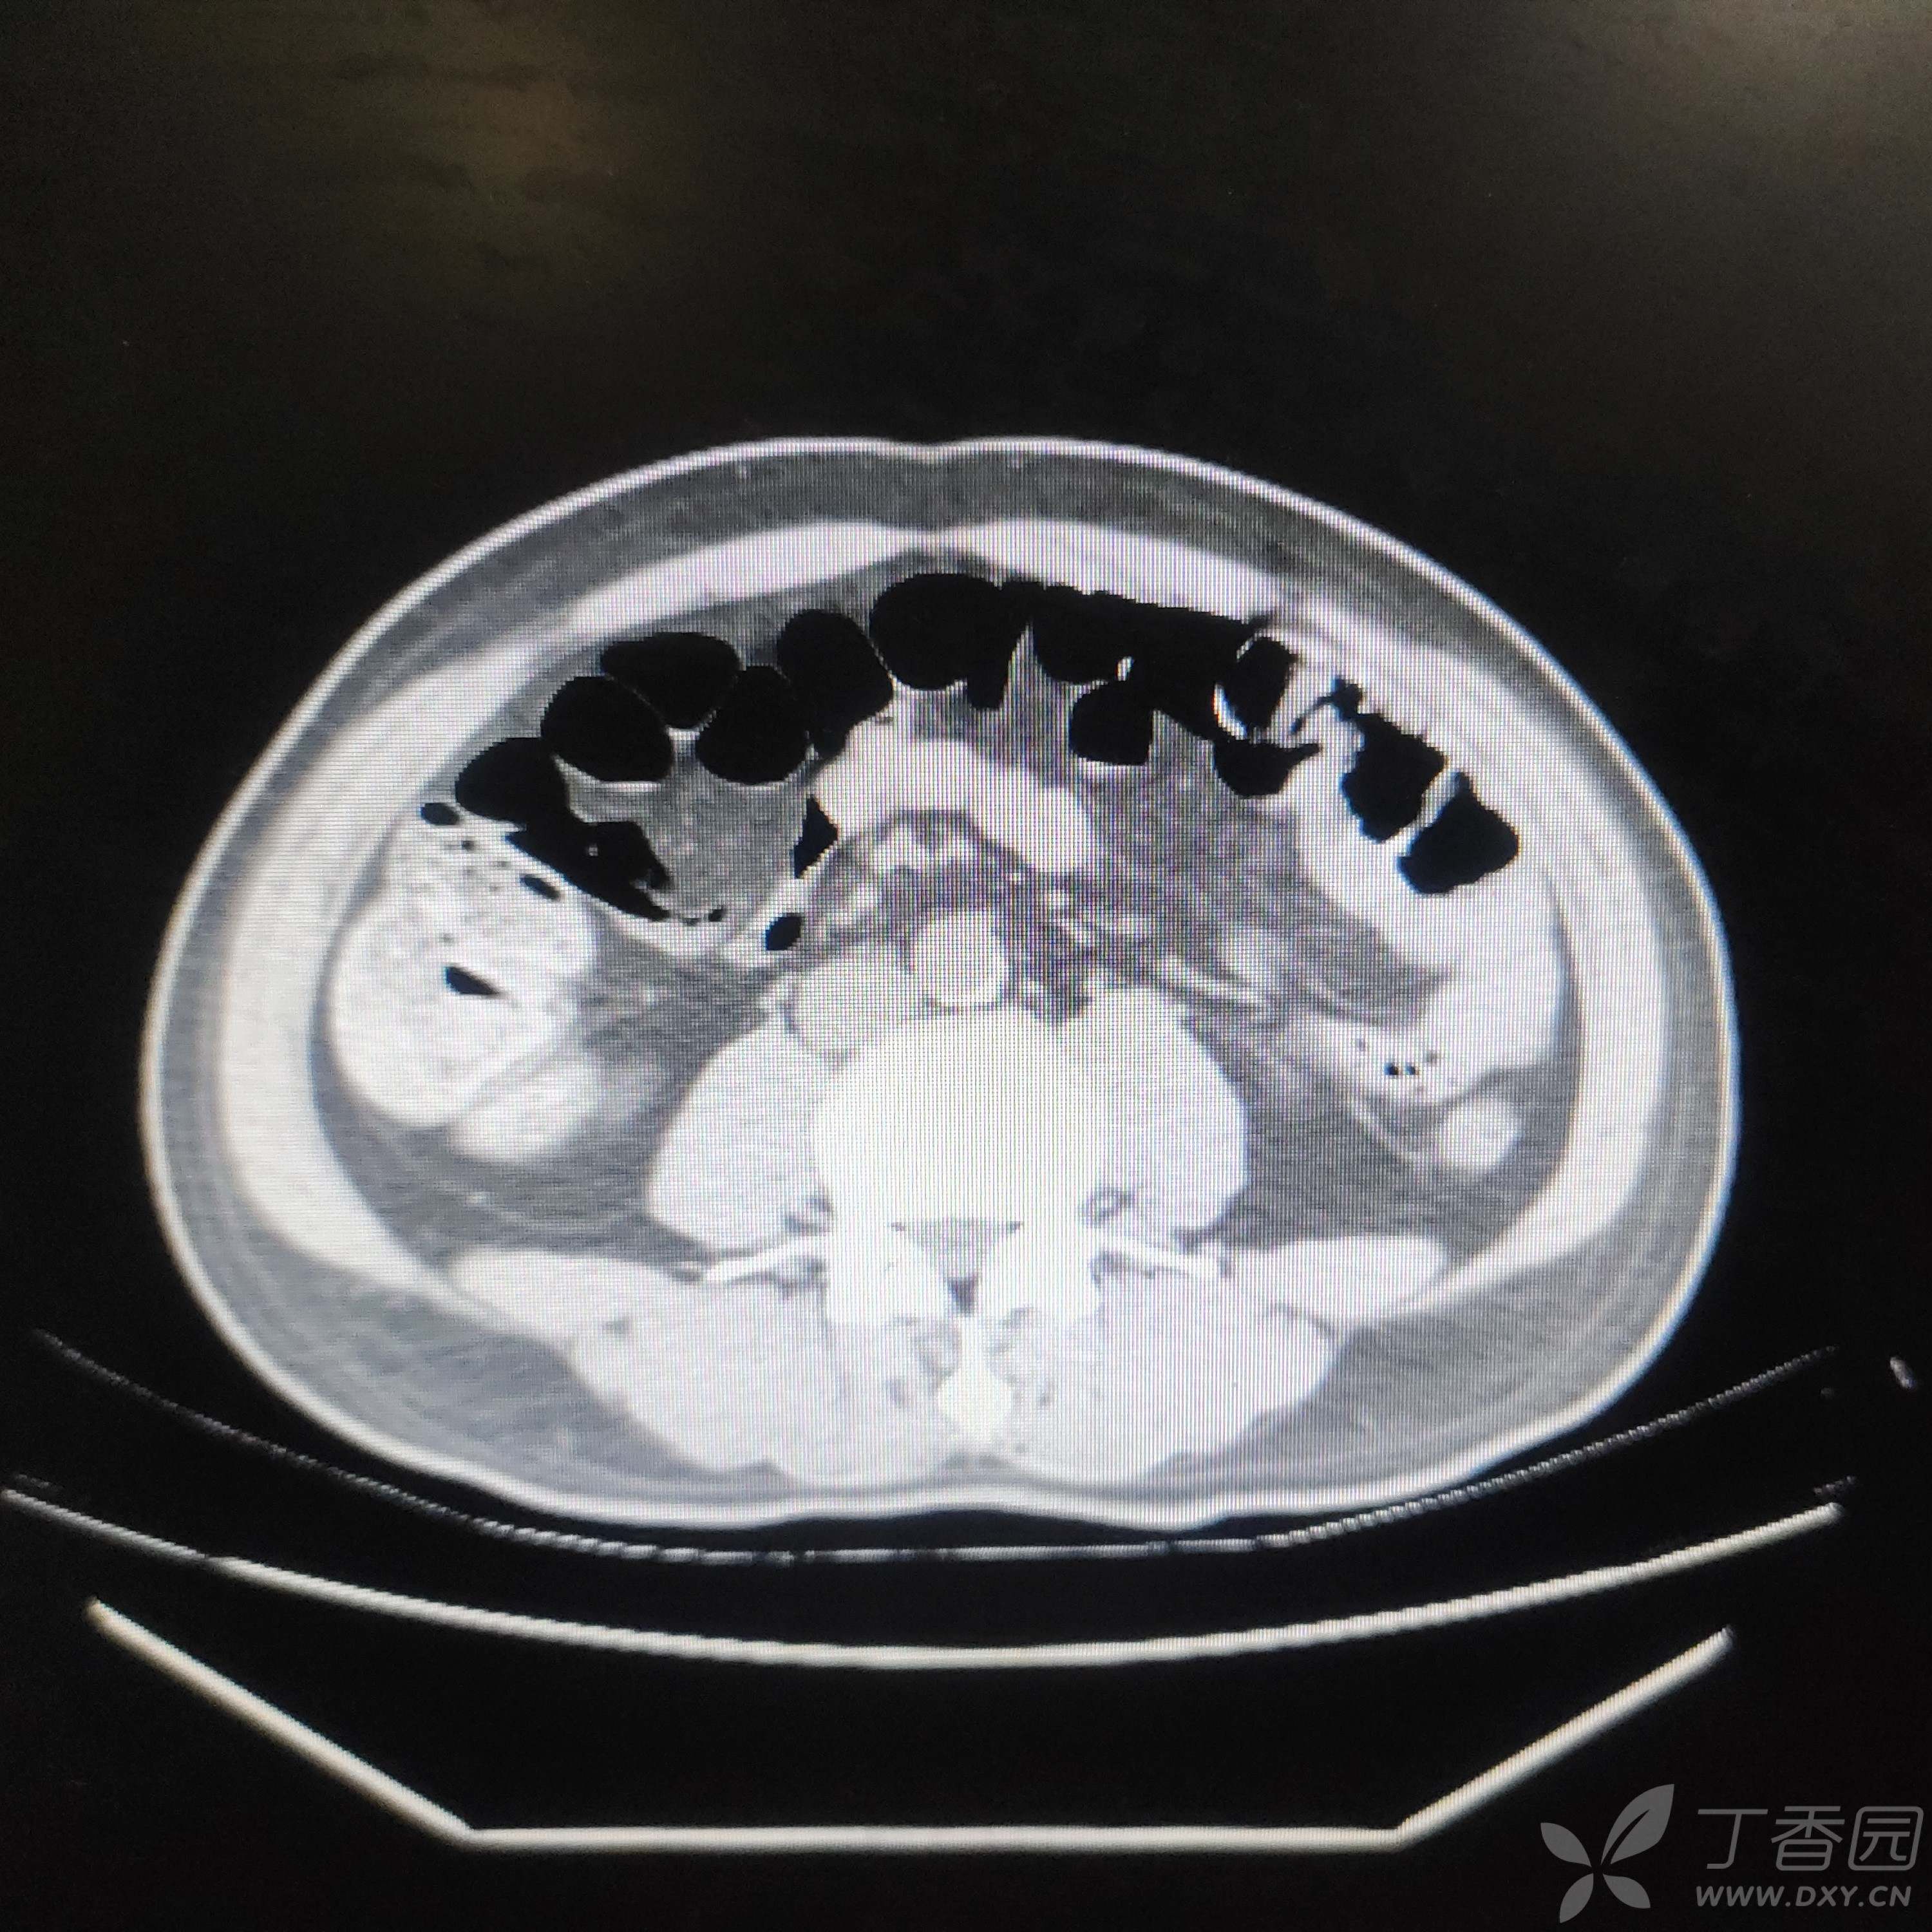

入院后血红蛋白进行性下降,正细胞性,1周内下降至74g/L,总胆29.7 umol/L,间胆22.5,CT肠管明显胀气(肠镜前空腹),未见占位,尿便常规、胃肠镜、胰腺增强MR、全腹盆腔CT未见责任病灶